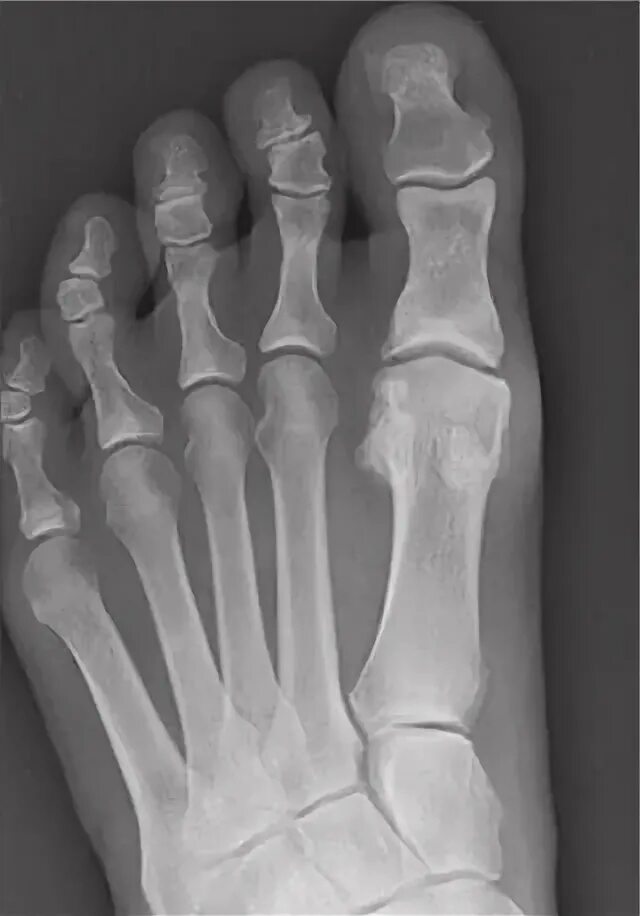

Артроз 1 степени плюснефалангового сустава стопы